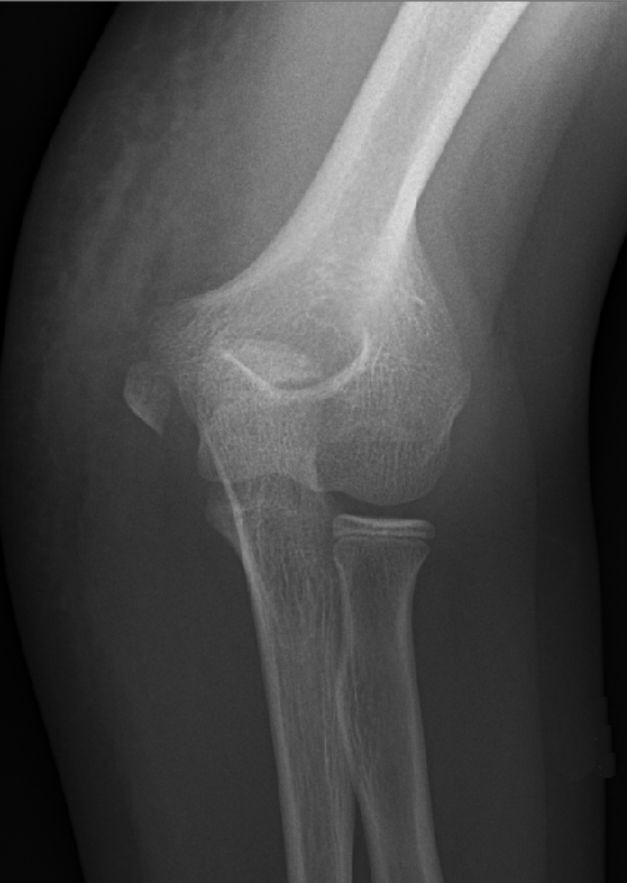

Suprakondylär humerusfraktur, Gartland 1.2, Rogers line delar capitulum radii, behandlades icke-kirurgiskt